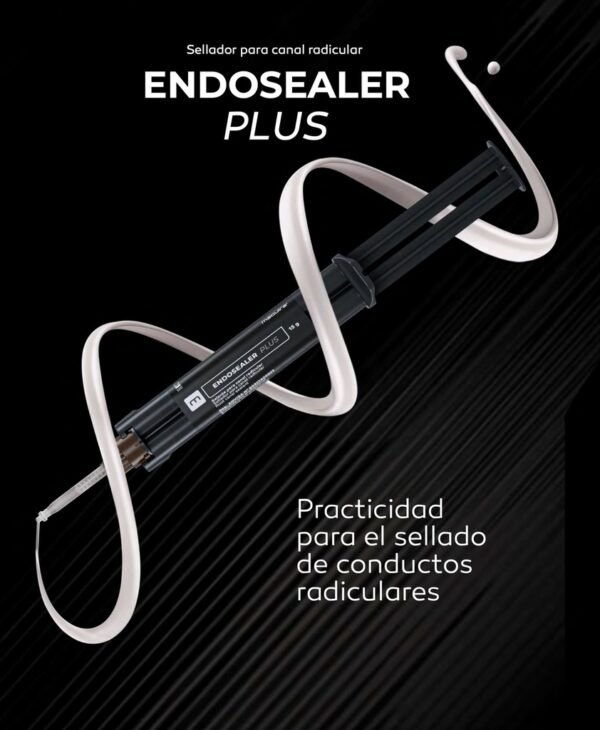

Endosealer Plus

Destinado para la obturación permanente de conductos radiculares en combinación con conos de gutapercha.

Endosealer Plus es un sellador de conductos radiculares con un sistema de reacción de resina epoxi-amina con propiedades físicas y químicas excepcionales. Presenta un sistema de homogeneización en puntas auto-mezcladoras, permitiendo la aplicación directa en el conducto radicular, ahorrando tiempo y material. Posee excelente radiopacidad, favoreciendo la observación del campo clínico en imágenes radiográficas.

Incluye: 1 Jeringa cuerpo doble con 15 g y 20 punteras aplicadoras.